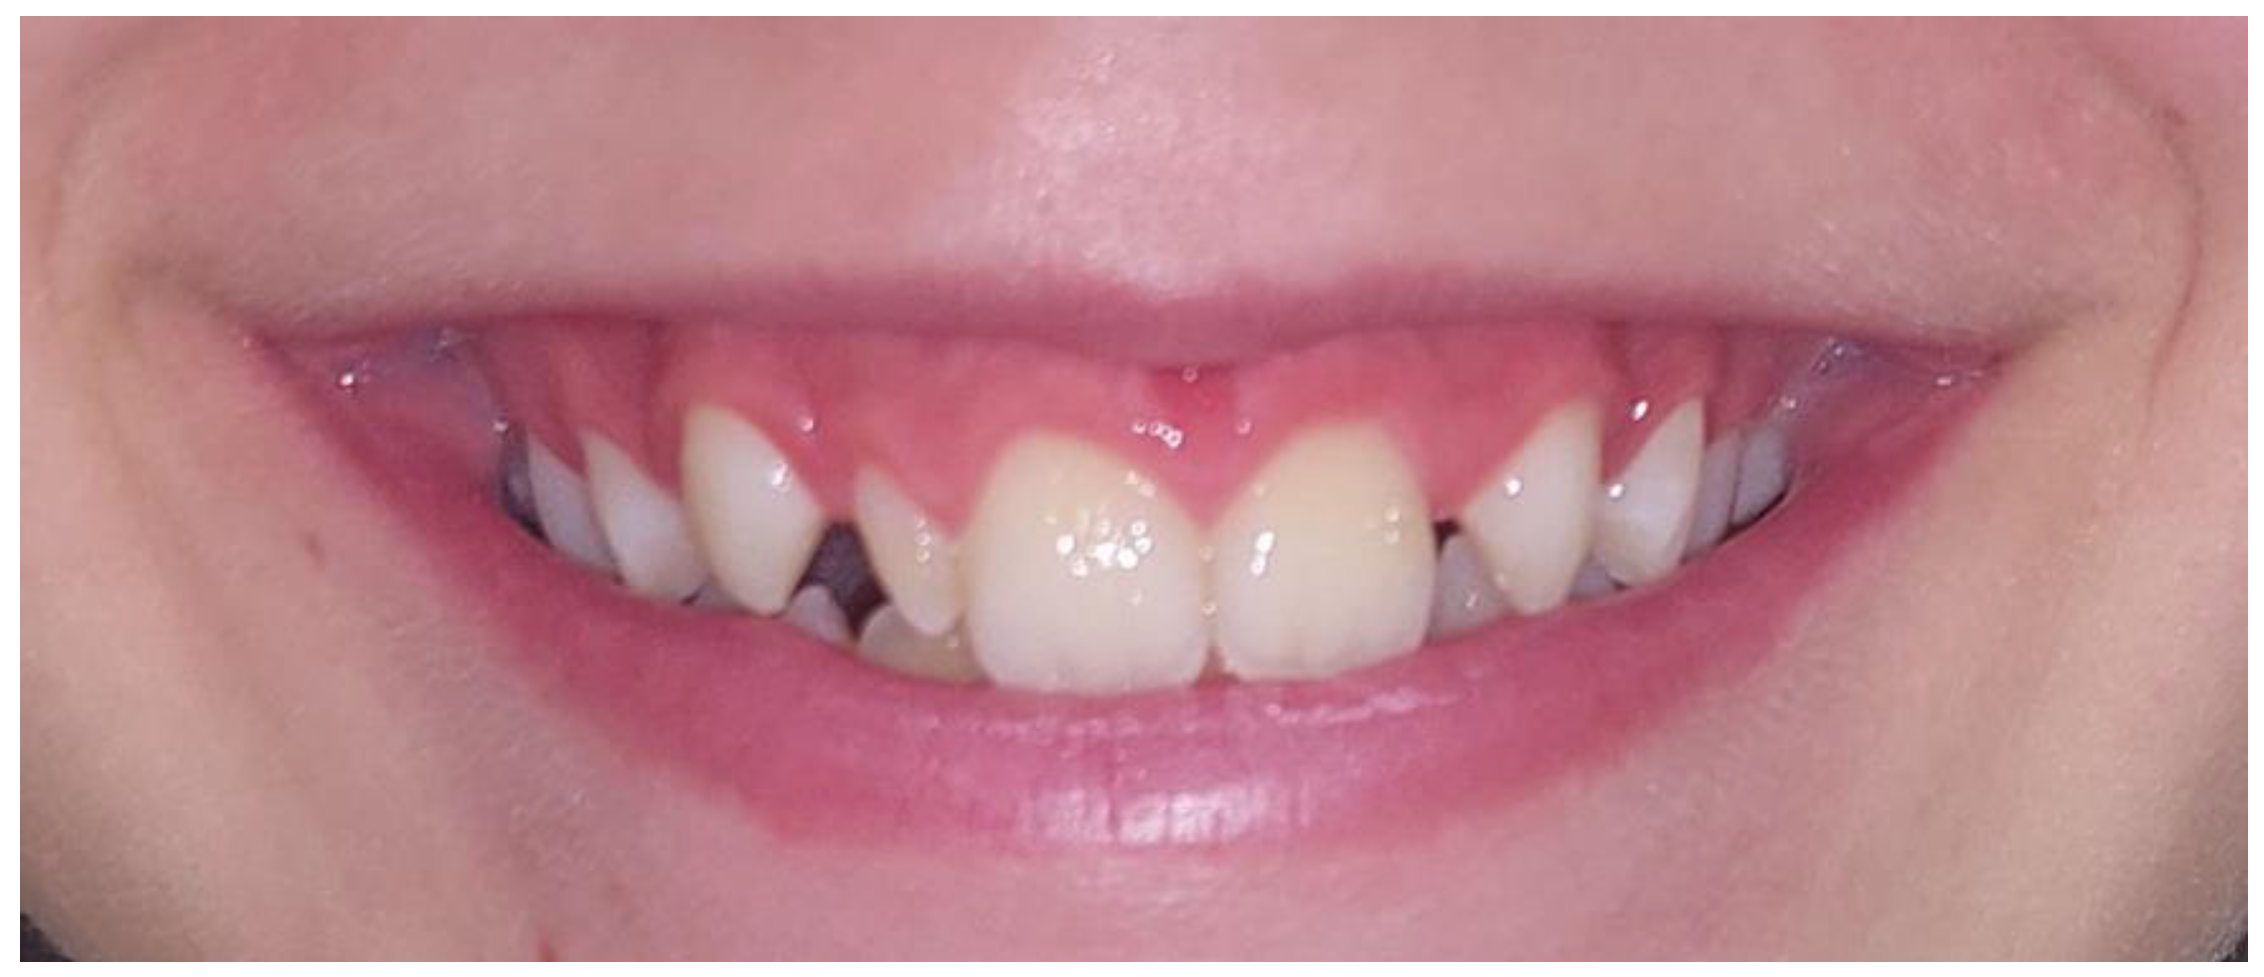

All 13 subjects with peg-shaped PMLI required additional treatment to achieve satisfactory aesthetics and function. Ten (76.9%) of them were treated conservatively by reshaping the tooth crown with composite by a restorative dentist (Figure 3), two (15.4%) subjects were treated with veneers by prosthodontist, and in one (7.7%) subject, the PMLI was extracted by an oral surgeon, space closed orthodontically and canine reshaped in PMLI. 11 (84.6%) subjects treated by restorative dentist, and all subjects treated with veneers by the prosthodontist and oral surgeon were satisfied with the treatment. Two subjects treated by a restorative dentist were dissatisfied with the treatment results and required retreatment.

Figure 3. Reshaping the dental crown with composite by a restorative dentist: (a) before and (b) after buildup.